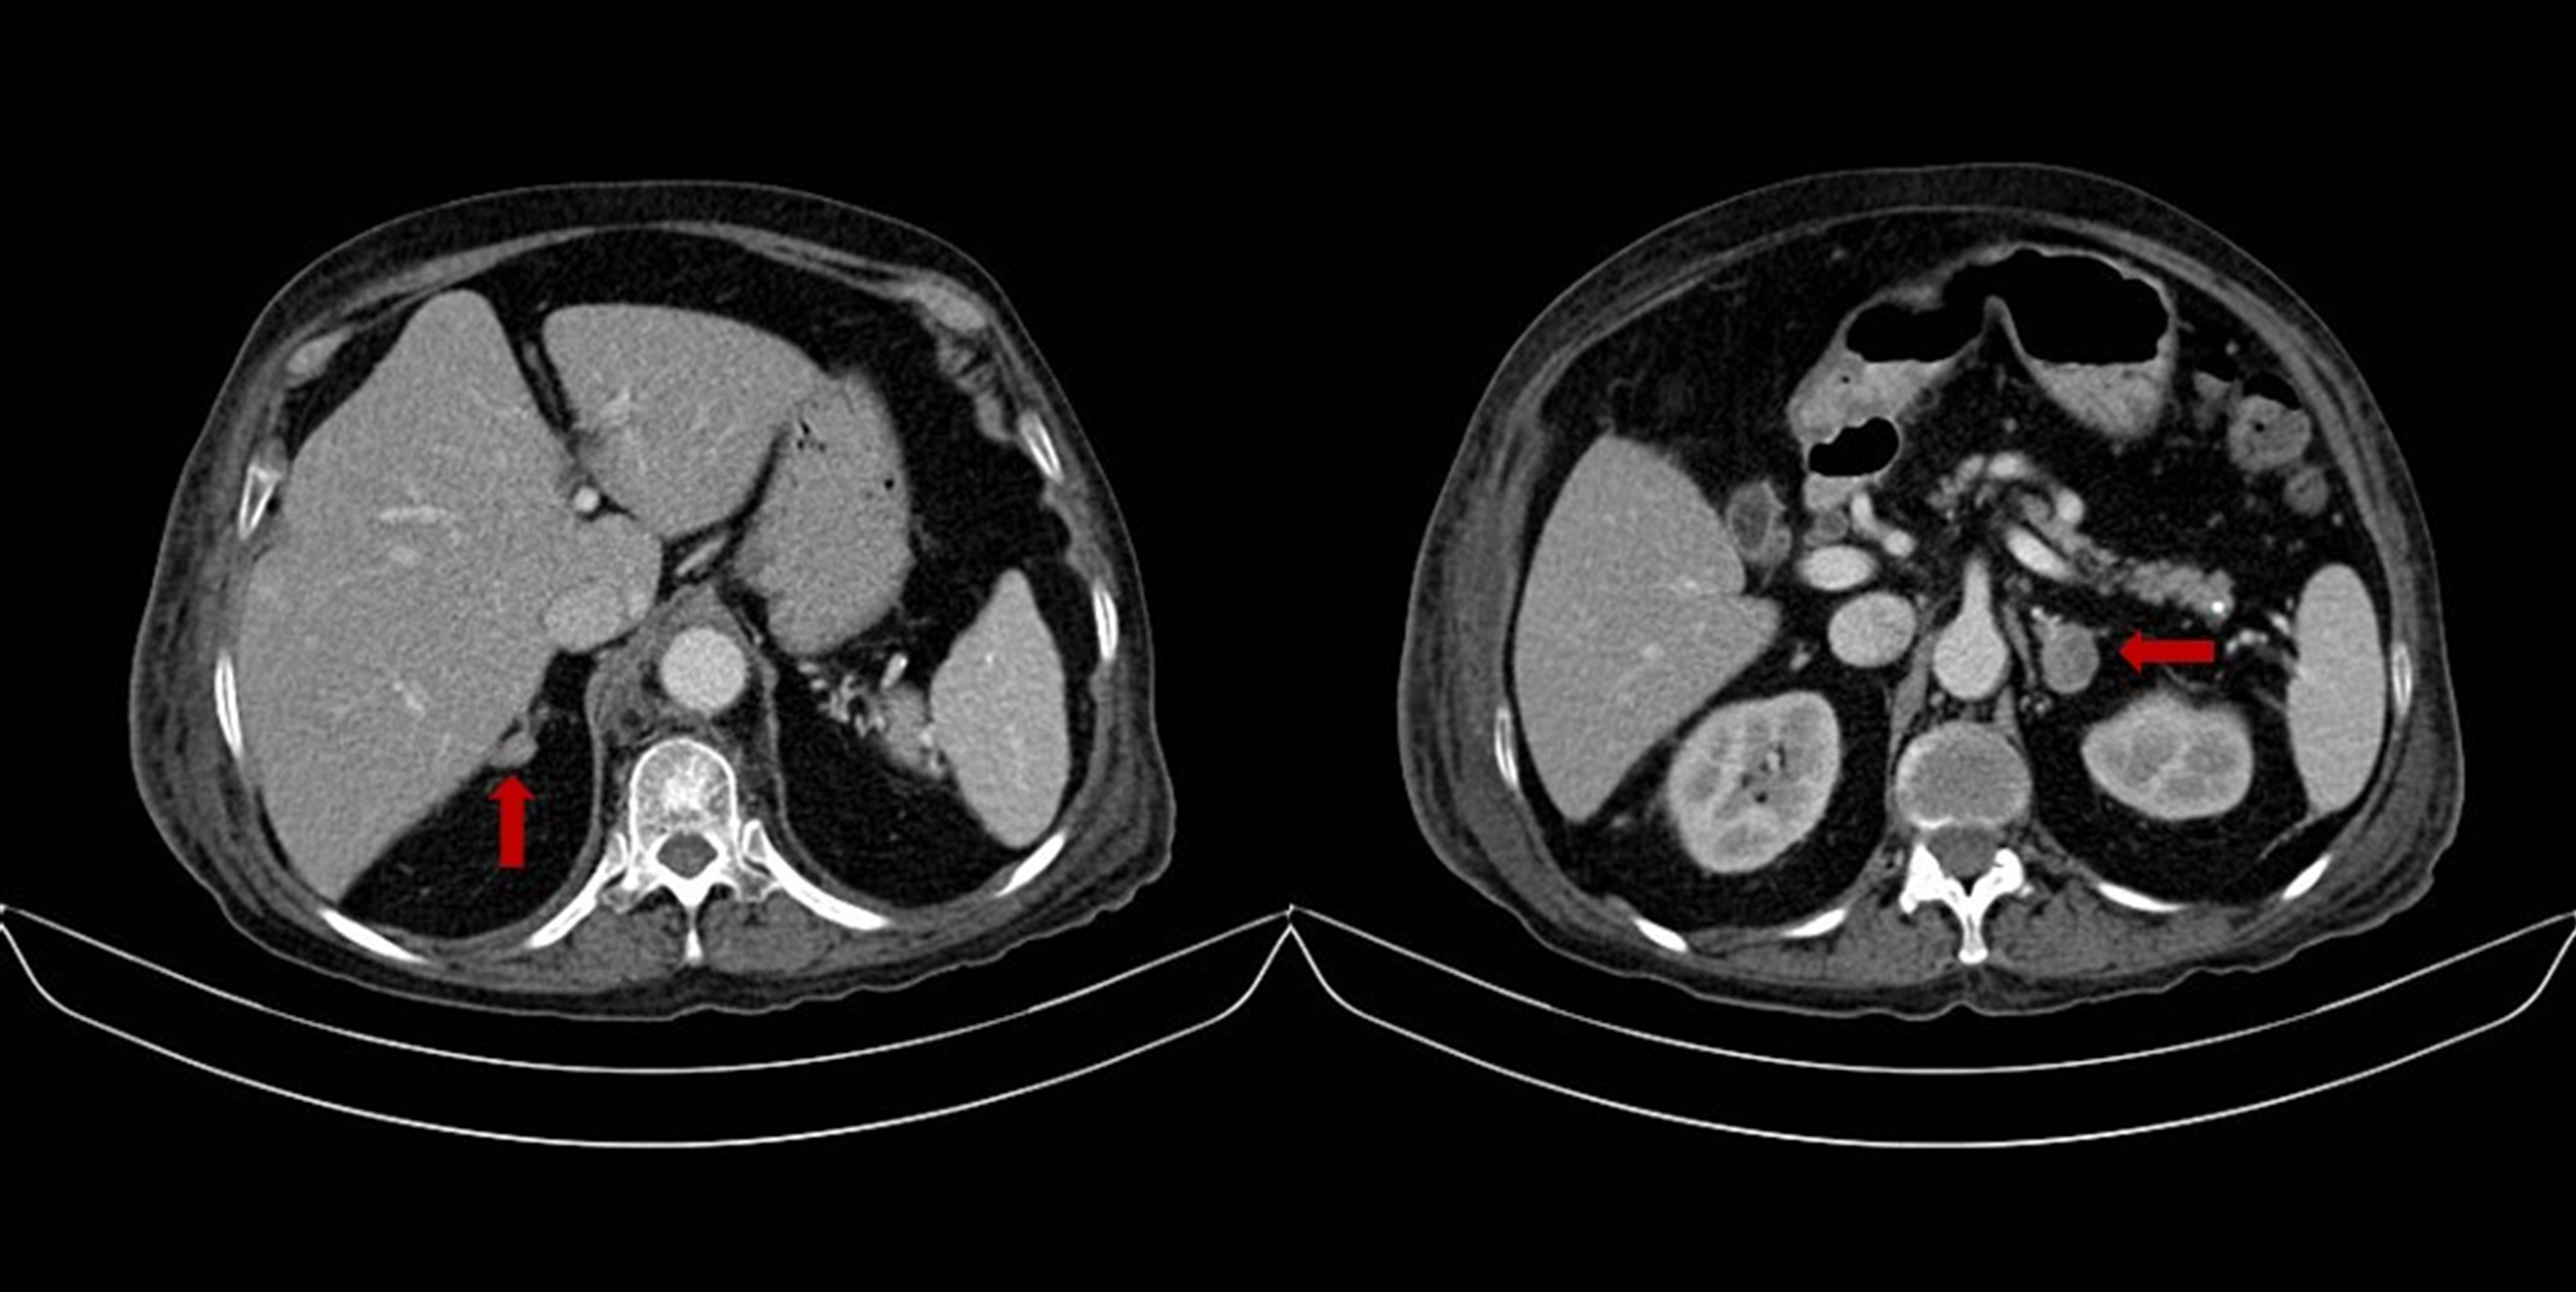

Figura 2.

Cateterismo de venas adrenales. A: Tronco común adrenal en donde confluyen la vena adrenal izquierda y la vena frénica inferior, que desembocan a la vena renal izquierda. B: Vena adrenal derecha con patrón glandular clásico, en donde se aprecia una vena adrenal central y ramas glandulares que confluyen hacia esta.

Se utilizó un protocolo descrito previamente 7 al cual se le realizaron algunas modificaciones, los autores proponen la medición de epinefrina como método para determinar la adecuada localización de los catéteres al momento de tomar la muestra, debido a que en nuestro medio no disponemos de medición de catecolaminas plasmáticas esta comprobación se realizó mediante la documentación radiográfica por venografía de la punta del catéter y se realizó medición de aldosterona para realizar las correcciones en la dilución que existen entre ambos lados 2. Se tomaron muestras de ambas venas adrenales y de la vena cava inferior (el procedimiento se muestra en la Figura 2 y los resultados se muestran en la Tabla 2). Basados en el modelo de interpretación del muestreo venoso adrenal propuesto por Young 3 se interpretó que la paciente cursaba con una hiperplasia adrenal con predominio en la producción de cortisol del lado derecho, se discutió con la pacientes y con el grupo quirúrgico el caso y se decidió entonces realizar una adrenalectomía bilateral. La paciente no presentó ninguna complicación posoperatoria y recibió terapia de reemplazo con hidrocortisona 50 mg cada 8 h durante las primeras 48 h y posteriormente recibió prednisolona 10 mg y fludrocortisona 0.1 mg como reemplazo con resolución de la hipokalemia. El resultado del estudio histológico de las glándulas fue compatible con una hiperplasia adrenal bilateral macro nodular.